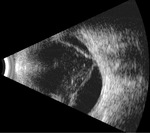

Rycina 8. Stan po zapaleniu wewnątrzgałkowym. Widoczne odwarstwienie siatkówki i odłączenie naczyniówki. Gałka oczna ze znaczną hipotonią